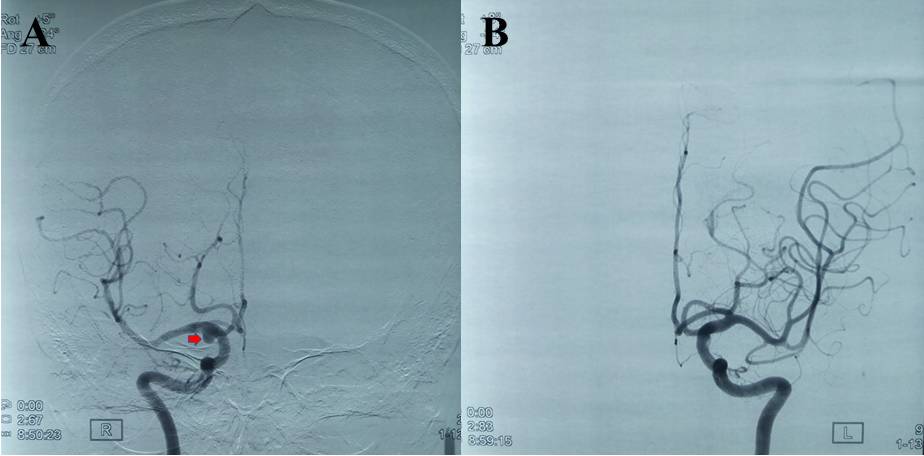

患者1月前因“肝肾多发囊肿并肾功能不全10年,加重1月”就诊于上海某医院,腹部MRI检查示肝肾多发囊肿(图1),予以护肾调节肾功能等对症支持治疗,住院期间(2017年4月15日)行头颅MRA检查提示:颅内动脉瘤。无头痛头晕,无肢体抽搐,无复视及视物模糊。半月后回当地医院进一步行全脑血管造影检查,提示:右侧后交通动脉瘤。为求进一步治疗,患者来我院就诊,门诊以“右侧后交通动脉瘤”收住病房。

图1. 外院腹部磁共振提示多脏器囊肿(肝,肾)。